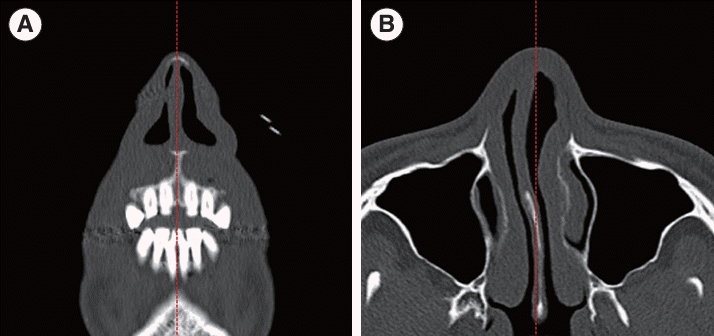

The parameters related to INVs were measured using conventional axial and coronal images from facial 3D CT scans, and the reformatted images were not used. Measurements were performed using a picture archiving and communication system (PACS; ZeTTA PACS; TaeYoung Soft Co. Ltd.) and the Aquarius workstation InTuition edition program (ver.4.4.12.249, TeraRecon Inc.). Before measurement, the INV level was determined by identifying the caudal margin of the upper lateral cartilage using scout navigation by scrolling through the images (Fig. 1). Although variations existed among the patients, the selected section typically corresponded to the first cut, where the scroll area disappeared and was anterior to the inferior turbinate. All measurement sections were confirmed via scout navigation and appropriately adjusted by reference to the anatomical variations [9].

Fig. 1.

Selected sections of facial computed tomography scans for internal nasal valve measurements. (A) Coronal view. (B) Axial view. The red dotted line indicates the midline.